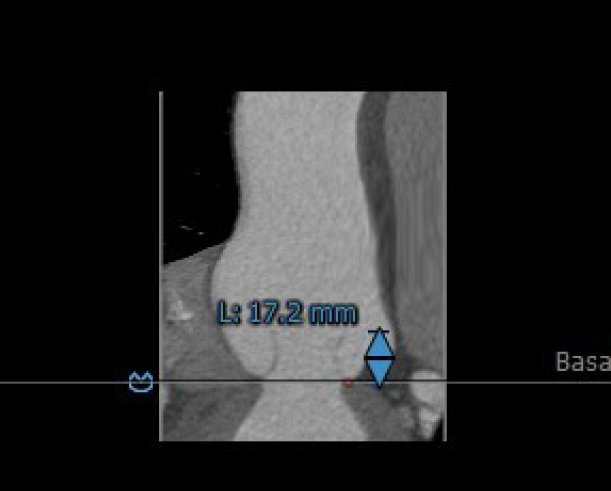

3.患者双侧冠脉开口高度可LCA:17.2mm,RCA:24.6mm。

左冠脉开口高度:17.2mm